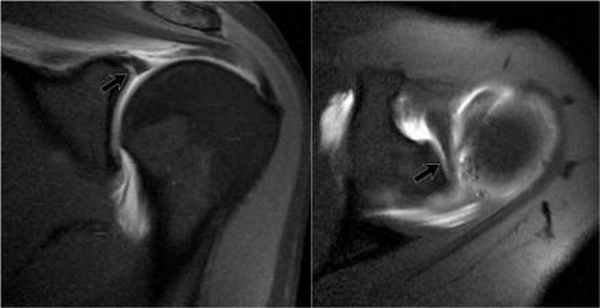

Передне-задняя артрограмма плеча, ротированного кнаружи: визуализируется нормальный косой контур прикрепления капсулы к анатомической шейке плечевой кости. Распространение контраста латеральнее данной линии и/или латеральнее большого бугорка указывает на разрыв вращательной манжеты. Обратите внимание на нормальное заполнение кармана двуглавой мышцы и подмышечного кармана. Передне-задняя артрограмма плеча, ротированного внутрь: визуализируется контраст, заполняющий подлопаточный карман. Подлопаточный карман (иначе называемый сумкой) образует сумку, перекидывающуюся через верхний край подлопаточной мышцы. Свободные тела часто мигрируют в нее или в подмышечный карман. Рисунок, вид спереди: показаны взаимоотношения мышц-вращателей плеча и интервала вращателей—участка треугольной формы, расширяющегося медиально и сужающегося латерально, с вершиной у переднего края большого бугорка. Показано сагиттальное сечение внутрисуставной части области плеча, удалена головка плечевой кости. Верхняя и средняя суставно-плечевая связки берут свое начало рядом с сухожилием двуглавой мыщцы, но верхняя суставно-плечевая связка имеет горизонтальное направление и образует часть петли сухожилия двуглавой мышцы. Средняя суставно-плечевая связка имеет косое нижнелатеральное направление и обеспечивает стабильность передней части. Пучки нижней суставно-плечевой связки берут свое начало около экватора суставной впадины лопатки спереди и сзади и образуют переднюю и заднюю границы подмышечного кармана. Схематично оказана нормальная анатомия интервала вращателей. Поперечные сечения в латеральной, средней и медиальной частях интервала вращателей представлены вдоль нижней части изображения. У латеральной части интервала, сразу проксимальнее входа в межбугорковую борозду плечевой кости, медиальный пучок клювовидно-плечевой связки (голубой цвет) и верхняя суставно-плечевая связка образуют петлю вокруг сухожилия длинной головки двуглавой мышцы. В средней части интервала вращателей клювовидно-плечевая связка покрывает верхнюю поверхность сухожилия двуглавой мышцы, а верхняя суставно-плечевая связка образует Т-образное соединение с клювовидно-плечевой связкой. Около медиального края интервала вращателей верхняя суставно-плечевая связка представляет собой округлую структуру, лежащую кпереди от сухожилия двуглавой мышцы; обе структуры покрыты U-образной клювовидно-плечевой связкой. Первая из шести выбранных косых корональных Т1ВИ МР-артрограмм, полученных вдоль оси сухожилия надостной мышцы. Задний пучок нижней суставно-плечевой связки образует толстый, четко различимый пучок по заднему краю подмышечного кармана. Задневерхняя губа суставной впадины лопатки часто имеет немного более высокую интенсивность сигнала, чем остальная часть, вероятно, вследствие артефакта «магического угла». Обратите внимание, что у этого пациента 20 лет в диафизе плечевой кости в первую очередь визуализируется кроветворный костный мозг, в то время как эпифиз содержит преимущественно желтый костный мозг. Очаги кроветворного костного мозга в диафизе плечевой кости сохраняются на протяжении всей жизни и могут быть ошибочно приняты за патологическое замещение. Кзади от начала двуглавой мышцы верхняя губа плотно прилежит к нижележащему суставному хрящу. Подмышечный карман четко очерчен и выступает за нижний край суставной впадины лопатки к шейке плечевой кости. Двуглавая мышца берет свое начало у надсуставного бугорка лопатки и крепится к верхней губе, затем следует латерально и кпереди над головкой плечевой кости и входите межбугорковую борозду плечевой кости. Визуализация места прикрепления длинной головки двуглавой мышцы плеча к суставной губе может различаться в зависимости от ротации плеча. В этом случае плечо ротировано кнаружи и проксимальная часть двуглавой мышцы располагается практически параллельно к плоскости визуализации. Трехстороннее отверстие визуализируется между сухожилием двуглавой мышцы и верхней губой. Эту находку кпереди от места прикрепления длинной головки двуглавой мышцы плеча к суставной губе не следует путать с повреждением верхней суставной губы лопатки спереди назад. Обратите внимание на нормальное распределение внутрисуставного контраста вдоль влагалища сухожилия двуглавой мышцы. Как правило, в передней проекции сустава визуализируется подлопаточный карман, выступающий над верхним краем подлопаточной мышцы. Обратите внимание на нормальное соединение сухожилия подлопаточной мышцы и самой мышцы. Также визуализируется наиболее передняя часть клювовидно-плечевой связки, сливающаяся с латеральными волокнами подлопаточной мышцы. На первой из шести отобранных Т1 FS МР-артрограмм визуализируется плечевой сустав в направлении сверху вниз. Сухожилие двуглавой мышцы проходит над головкой плечевой кости. Клювовидно-суставная связка визуализируется частично, сплетаясь с клювовидно-плечевой связкой. Клювовидно-плечевая связка имеет средний пучок, который образует часть петли сухожилия двуглавой мышцы, и латеральный пучок, который перекидывается через передний край подлопаточной мышцы и крепится к подлопаточной мышце, а также к малому и большому бугоркам, формируя таким образом часть поперечной связки. В литературе обсуждается вопрос, является ли поперечная связка самостоятельной структурой. Она представляет собой слияние волокон подлопаточной мышцы и петли сухожилия двуглавой мышцы, удерживает сухожилие двуглавой мышцы в межбугорковой борозде. Передняя и задняя губы прилежат к хрящу на передней поверхности суставной впадины. Задняя губа не имеет сублабральной борозды и жидкость между суставным хрящом и губой всегда наблюдается в норме. Средняя суставно-плечевая связка прилежит к заднему краю сухожилия подлопаточной мышцы, с которым сливается в нижней части. Площадка истонченного хряща суставной впадины лопатки в норме расположена центрально и известна как «голая зона». Здесь часто располагаются выступающие кровеносные сосуды кзади от головки плечевой кости, которые иногда ошибочно принимают за субхондральные кисты. Анализ округлых участков на последовательных снимках поможет установить их тубулярное строение, что соответствует сосудистым структурам. При визуализации места прикрепления передней части капсулы сустава к лопатке отмечается значительная вариабельность. В норме в данной области глубже подлопаточной мышцы наблюдается небольшой карман. Подмышечная петля состоит из множества пучков с участками небольшого расхождения между ними. Это создает слоистый вид в месте их прикрепления к шейке плечевой кости. Обратите внимание, что хотя верхняя часть подлопаточной мышцы фиксирована к плечу посредством сухожилия, нижняя-крепится посредством мышечной ткани. Первая из девяти отобранных сагиттальных PD FS МР-артрограмм, от латеральной к медиальной: визуализируется нормальная вращательная манжета в виде кольца по типу велосипедной шины вокруг верхней и задней поверхностей головки плечевой кости. Небольшие разрывы сухожилия надостной мышцы часто возникают в переднем или «ведущем» крае, который лучше визуализируется в сагиттальной проекции. Обратите внимание на высокоинтенсивный сигнал в области дельтовидной мышцы, отражающий наличие лидокаина, введенного во время процедуры. Последовательность PD FS позволяет визуализировать контрастное вещество и другие жидкости с высокоинтенсивным сигналом. Визуализируется подлопаточная мышца, которая прикрепляется к малому бугорку. Сухожилие двуглавой мышцы находится сразу выше данного участка при изгибе и вступлении в межбугорковую борозду. Клювовидно-плечевая связка лежит выше двуглавой; она и поверхностные волокна подлопаточной мышцы сливаются, образуя поперечную связку межбугорковой борозды. Сагиттальная плоскость лучше подходит для оценки внутрисуставного расположения сухожилия двуглавой мышцы, поскольку эффект частичного объема затрудняет точную визуализацию в корональной и аксиальной плоскостях. Обратите внимание, что подлопаточная мышца имеет множественные сухожильные волокна, чередующиеся с мышечными, а нижняя треть- мышечное прикрепление к малому бугорку. На этом уровне начинает визуализироваться подлопаточный карман, простирающийся над верхним краем подлопаточной мышцы. Передний и задний пучки нижней суставно-плечевой связки определяются в месте прикрепления к хирургической шейке плечевой кости. Клювовидно-плечевая связка представлена широким пластом и делится на медиальный и латеральный пучки. Подмышечный карман имеет множество пучков, что создает исчерченный вид. Клювовидно-плечевая связка заполняет интервал вращателей и перекидывается через верхнюю часть сухожилия двуглавой мышцы. Латеральный пучок визуализируется в месте прикрепления к переднему краю подлопаточной мышцы. Клювовидно-плечевая связка и клювовидно-суставной пучок визуализируются в месте их начала у основания клювовидного отростка. Их визуализация в значительной степени вариабельна. В норме визуализируются множественные карманы сустава: подмышечный, задний и подлопаточный (часто именуемый подлопаточной сумкой). Снимок получен медиальнее предыдущего, но у другого пациента; вследствие большего растяжения полости сустава достигнута лучшая визуализация карманов сустава и суставно-плечевых связок. Суставная губа визуализируется частично. Хотя сагиттальный срез не является первостепенным для оценки губы, на этом уровне наличие контрастного вещества между костью и губой подтверждает разрыв губы. На аксиальной Т1 МР-артрограмме визуализируется сублабральное окно. Этот вариант нормы имеет место в передневерхнем квадранте губы, где редко возникают изолированные разрывы губы. Они не распространяются ниже уровня клювовидного отростка. В отличие от неровного зазубренного контура при разрыве губы, сублабральное окно имеет ровный контур. На аксиальной Т1 МР-артрограмме визуализируется сублабральное окно (другой пациент). Снимки получены ниже для дифференцировки между губой и сублабральным окном (в этом случае верхняя губа присоединяется к кости более низко) или комплексом Буфорда (в этом случае тяжистая средняя суставно-плечевая связка сливается с подлопаточной мышцей и отдельная верхняя губа визуализируется более низко). Артроскопия: визуализируется прочно прикрепленная суставная губа кзади от места прикрепления длинной головки двуглавой мышцы плеча к суставной губе и сублабральное окно в передневерхнем квадранте сустава. На рисунке в сагиттальной плоскости показан комплекс Буфорда: передняя верхняя суставная губа отсутствует, средняя суставно-плечевая связка утолщена и натянута. На аксиальной Т1 FS МР-артрограмме визуализируется комплекс Буфорда. Средняя суставно-плечевая связка утолщена и натянута. Такое строение может быть немного нестабильным, так как пациенты с комплексом Буфорда имеют повышенный риск повреждения верхней суставной губы лопатки спереди назад. На аксиальной Т1 FS МР-артрограмме у пациента с комплексом Буфорда на этом уровне определяется наличие губы, средняя суставно-плечевая связка остается натянутой.

• Передняя губа: комплекс Буфорда, борозда или пространство под губой

• Варианты строения верхней губы: верхняя губа может иметь менисковидную форму в месте прикрепления к ней длинной головки двуглавой мышцы плеча и кпереди от нее

Подгубное отверстие

Подгубное отверстие - отсутствие прикрепления передневерхних отделов суставной губы в области 1-3 часов.

Определяется у 11% населения.

При МР-артрографии подгубное отверстие не должно приниматься за подгубное углубление или SLAP-поврежедение, которые также локализуются в данной области.

Подгубное углубление расположено в области прикрепления сухожилия двуглавой мышцы плеча на 12 часов и не распространяется на область 1-3 часов.

SLAP-повреждение может распространятся на область 1-3 часов, но всегда должно быть вовлечено прикрепление сухожилия двуглавой мышцы.

Пролистывайте изображения и обратите внимание суставная губа не прикреплена в области 12-3 часа, в области подгубного отверстия.

Обратите внимание гладкие края, в отличии от SLAP-повреждения.